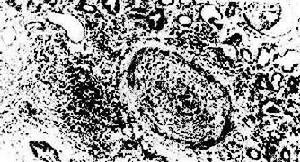

成年人腎實質厚度約1.5~2cm,老年人亦無明顯差異,2.0cm為增厚。據調查以腎臟長徑加腎實質厚度測量鑑別急性和慢性腎功能衰竭,符合率達92.6%。患了慢性腎臟病,定期檢查腎大小,可助監測病變進展。

單側腎萎縮臨床特點

(1)對側腎臟代償性增大不常見,但腎血流量多數增強。(2)單側腎萎縮本身不引起高血壓,如先天性腎發育不良、腎自截、腎結核、慢性腎盂腎炎不伴高血壓,但腎動脈狹窄因激活腎素-血管緊張素-醇固酮系統而使血漿腎素水平升高[4],引起高血壓常見。

(3)腎動脈狹窄伴患肢足背動脈搏動減弱或消失並不常見。

(4)腎動脈狹窄經DSA擴張術後,萎縮腎臟血流明顯增加,腎臟較前明顯增大,可見部分萎縮腎臟具有可逆性。

(5)腎動脈嚴重狹窄,探及不到血流,但通過側枝循環使腎臟保持良好血供,不致病腎嚴重萎縮。

(6)在同位素腎圖上,病腎顯影延遲,排泄減慢,以排泄功能異常為先出現。腎血流明顯減少或消失。